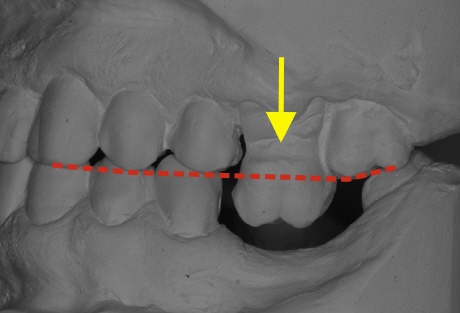

Das Bild oben zeigt eine jahrelang bestehende Lückensituation. Nur ein Zahn feht, dies hat jedoch mit den Jahren dazu geführt, dass der nicht abgestützte Zahn (gelber Pfeil) aus seinem Zahnfach dem Unterkiefer entgegen wächst. Die gestrichelte rote Linie zeigt die Kauebene, die von den Höckerspitzen im Normalfall berührt werden und zeigt eindrucksvoll die enormen Veränderungen. Man spricht in diesem Fall von einer instabilen Situation da sich immer weitere Veränderungen ergeben. Bei Mahlbewegungen ist dieser Zahn sogar ein Hinderniss, das das Zahnzusammenspiel gestört ist. In dieser fortgeschrittenen Situation ist der obere Zahn kaum noch zu retten und muß entfernt werden.